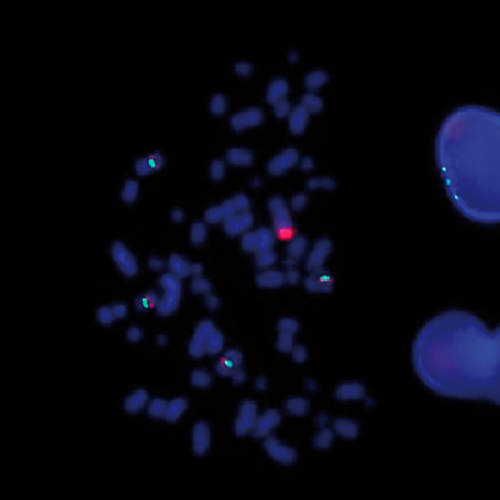

IVD FUS Break product photo

IVD FUS Break

or REQUEST a bulk quote.